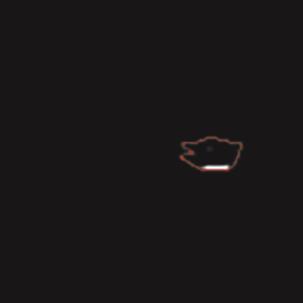

基于逐通道空间自适应选择核卷积与双向边界感知机制的乳腺超声图像病变分割网络

A Breast Ultrasound Images Lesion Segmentation Network Based on Channel-Wise Spatially Adaptive Selective Kernel Convolution and Bidirectional Boundary-Aware Mechanism

乳腺癌是全球女性最常见的恶性肿瘤之一,准确的病变分割对于乳腺癌的早期诊断与治疗具有重要意义。然而,由于病变形态的多样性以及超声成像机制的复杂性,现有基于深度学习的乳腺超声图像病变分割方法在分割准确性方面仍面临巨大挑战。为进一步提升乳腺超声图像中病变区域的分割精度,该文基于经典U-Net架构,提出了一种新型乳腺超声图像病变分割网络(CWSASKM-BBAM-Net)。首先,在网络中引入逐通道空间自适应选择核卷积模块(CWSASKM),根据不同通道的语义特征为每个空间位置自适应选择感受野大小,以增强多尺度信息的建模能力;然后,引入双向边界感知机制(BBAM),通过融合正向与反向注意力,对目标显著区域及其边界进行协同建模,同时逐步提升对非显著区域与病变区域的区分能力,以进一步强化边界信息的表达;最后,在3组公开乳腺超声图像数据集(BUSI、UDIAT和STU)上开展分割实验。结果表明:该方法在数据集BUSI上的杰卡德指数、精确率、召回率和Dice相似系数分别为71.97%、82.85%、81.40%和80.44%,较次优方法分别提升1.69、1.05、1.28和1.84个百分点;在数据集UDIAT上,这4项指标分别达到78.14%、88.31%、86.73%和86.10%,较次优方法分别提升了2.75、2.04、0.56和2.01个百分点;在外部数据集STU上,该方法也取得了优于其他方法的整体表现。实验结果表明,CWSASKM-BBAM-Net在乳腺超声图像分割任务中展现出更优的整体性能。